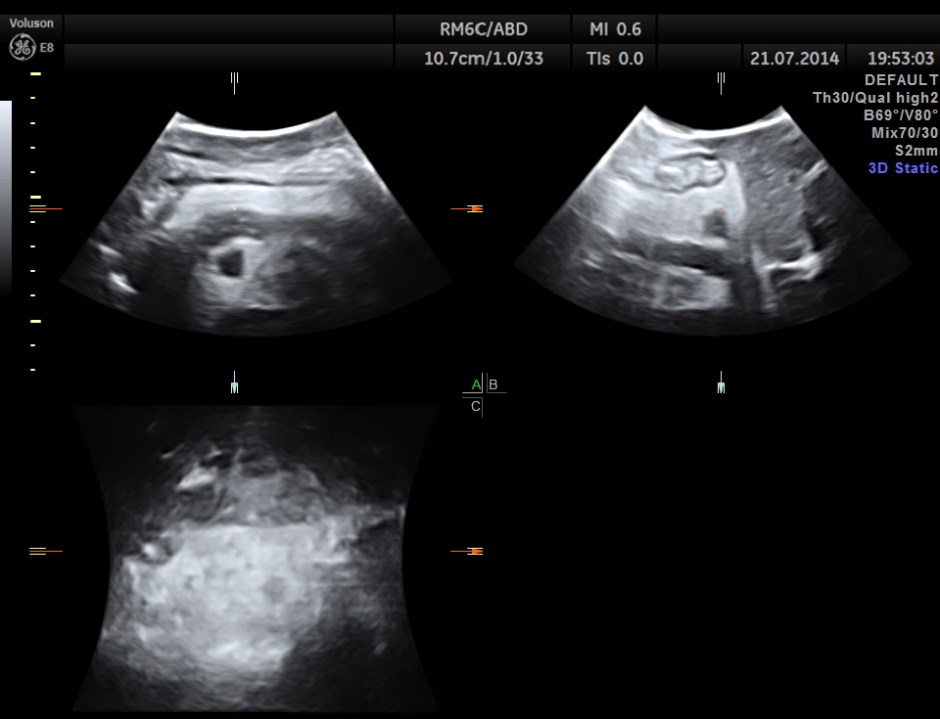

His abdominal ultrasound pictures are given below.

The following pictures show the pancreas.

Pancreatic duct is dilated prominently.

Pancreatic calculi are seen.